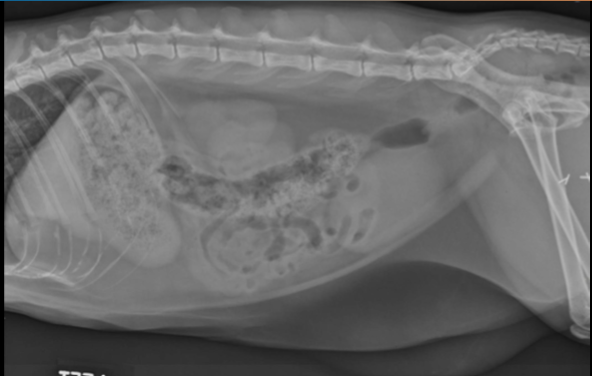

Label the kidneys and bladder

A

Identify the kidneys What pathology is present?